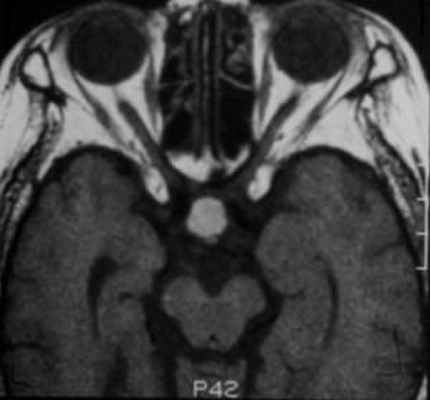

![f3]()

Т2-взвешенное аксиальное изображение: изоинтенсивное коре образование (тот же пациент, что и на предыдущем изображении).